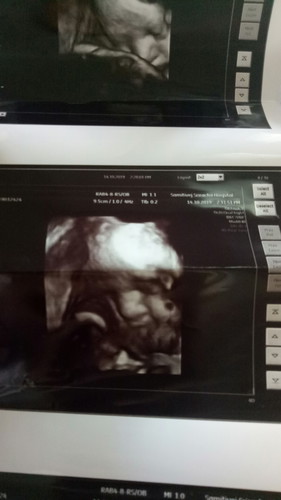

ตอนนี้ออยตั้งครรภ์ 37 วีคแล้วค่ะอยากให้แม่ๆช่วยวิจาร์หน่อยค่ะว่าน้องจะมีจมูกโด่งไหมค่ะและตอนนี้ออยทั้งไอทั้งอาเจียนไอจนเจ็บท้องไปหมดจะมีผลต่อลูกออยไหมค่ะ

ถ้ามองไม่ผิดจมูกโด่งมากค่ะแม่